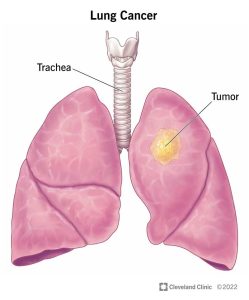

شکل 1. نمونهای از تومور موجود در ریه که توسط پیکانی بر روی رادیوگرافی قفسه سینه نشان داده شدهاست.

سرطان ریه معمولاً در مجاری هوایی (برونش یا برونشیول) یا کیسههای هوایی کوچک (آلوئول) ریههای شما شروع میشود. سپس میتواند به سایر اندامها گسترش یابد.

سرطان ریه نامی است که برای سرطانهایی که از ریههای شما شروع میشوند – معمولاً در مجاری هوایی ( برونش یا برونشیول) یا کیسههای هوایی کوچک (آلوئول) – به کار میرود. سرطانهایی که از جاهای دیگر شروع میشوند و به ریههای شما میرسند، معمولاً بر اساس محل شروعشان نامگذاری میشوند (ممکن است پزشک شما این نوع سرطان را سرطانی که به ریههای شما متاستاز داده است، بنامد (1).